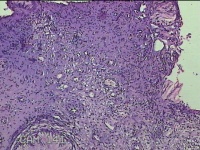

宫颈组织

性别

女

年龄

31岁

临床诊断

宫颈上皮内瘤变

一般病史

发现宫颈CIN2 2个月。

标本名称

大体所见

灰白暗红色组织2.8x1.8x0.3cm一块,表面糜烂,切面灰白暗红色,质软。

所提供图片不具有诊断价值。